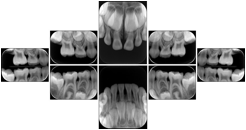

Intra-oral radiography typically involves acquisition of multiple images of various parts of the dentition. Many digital radiographic systems offer customized templates that are used for displaying the images in a study on the screen. These templates may also be referred to as mounts or view sets. The Structured Display Object represents a standard method of encoding and exchanging the layout and intended display of Structured Displays. A structured display object created in this manner could be stored with a study and exchanged with images to allow for complete reproduction of the original exam.

1. A patient visits a General Dentist where a Full Mouth Series Exam with 18 images is acquired. The dentist observes severe bone loss and refers the patient to a Periodontist. The 18 images from the Full Mouth Series along with a Structured Display are copied to a DICOM Interchange CD and sent with the patient to see the specialist. The Periodontist uses the CD to open the exam in his Dental Radiographic Software and consults via phone with the General Dentist. Both are able to observe the same exam showing the images on each user's display using the exact same layout.

Intra-oral Full Mouth Series Structured Display

Figure OO-1. Intra-oral Full Mouth Series Structured Display